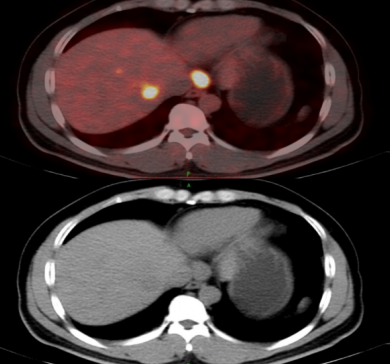

邱素芳主任医师团队接诊了他。为了确诊病情,程先生接受了PET-CT全身扫描,结果显示肝脏和腹膜后淋巴结均有转移灶。随后,通过肝穿刺病理检查和免疫组化,医生们证实了肝转移的原发病灶在鼻咽癌。

2022.03.11PET-CT:肝VIII段低密度影,大小约3.7cm×2.8cm